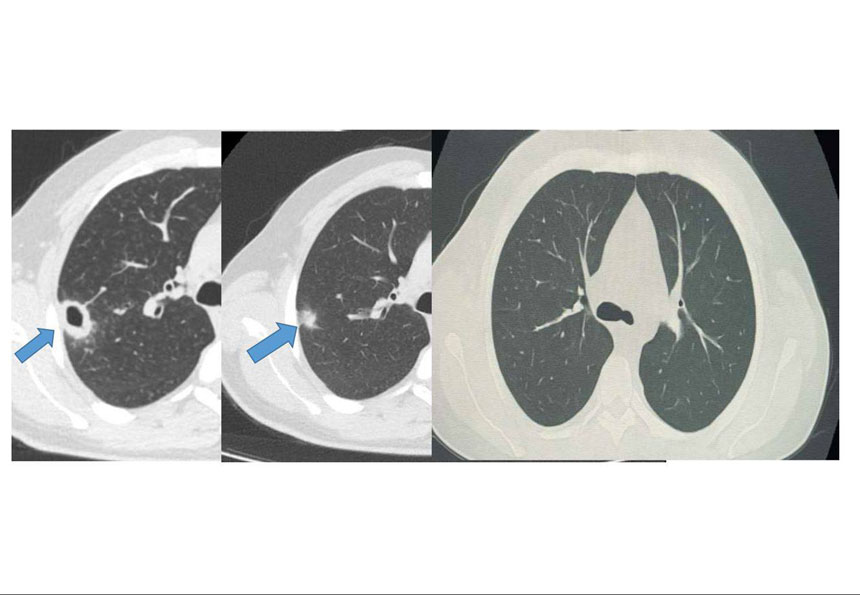

Bayburt Postası - Göğüs Hastalıkları Uzmanı Uzm. Dr. Hilal Sayma tarafından muayene edilen hastanın akciğerinde kitle benzeri bir doku tespit edildi. Bu durum üzerine ileri tetkik amacıyla hastaya bronkoskopi işlemi uygulandı.

Bronkoskopi sonuçları, tespit edilen lezyonun kanser veya tüberküloz gibi ciddi hastalıklarla ilişkili olmadığını ortaya koydu.

Tanının konulmasının ardından hasta için uygun tedaviye başlandı. Sadece iki haftalık tedavi sürecinin sonunda yapılan kontrollerde, akciğerdeki lezyonun neredeyse tamamen gerilediği belirlendi.